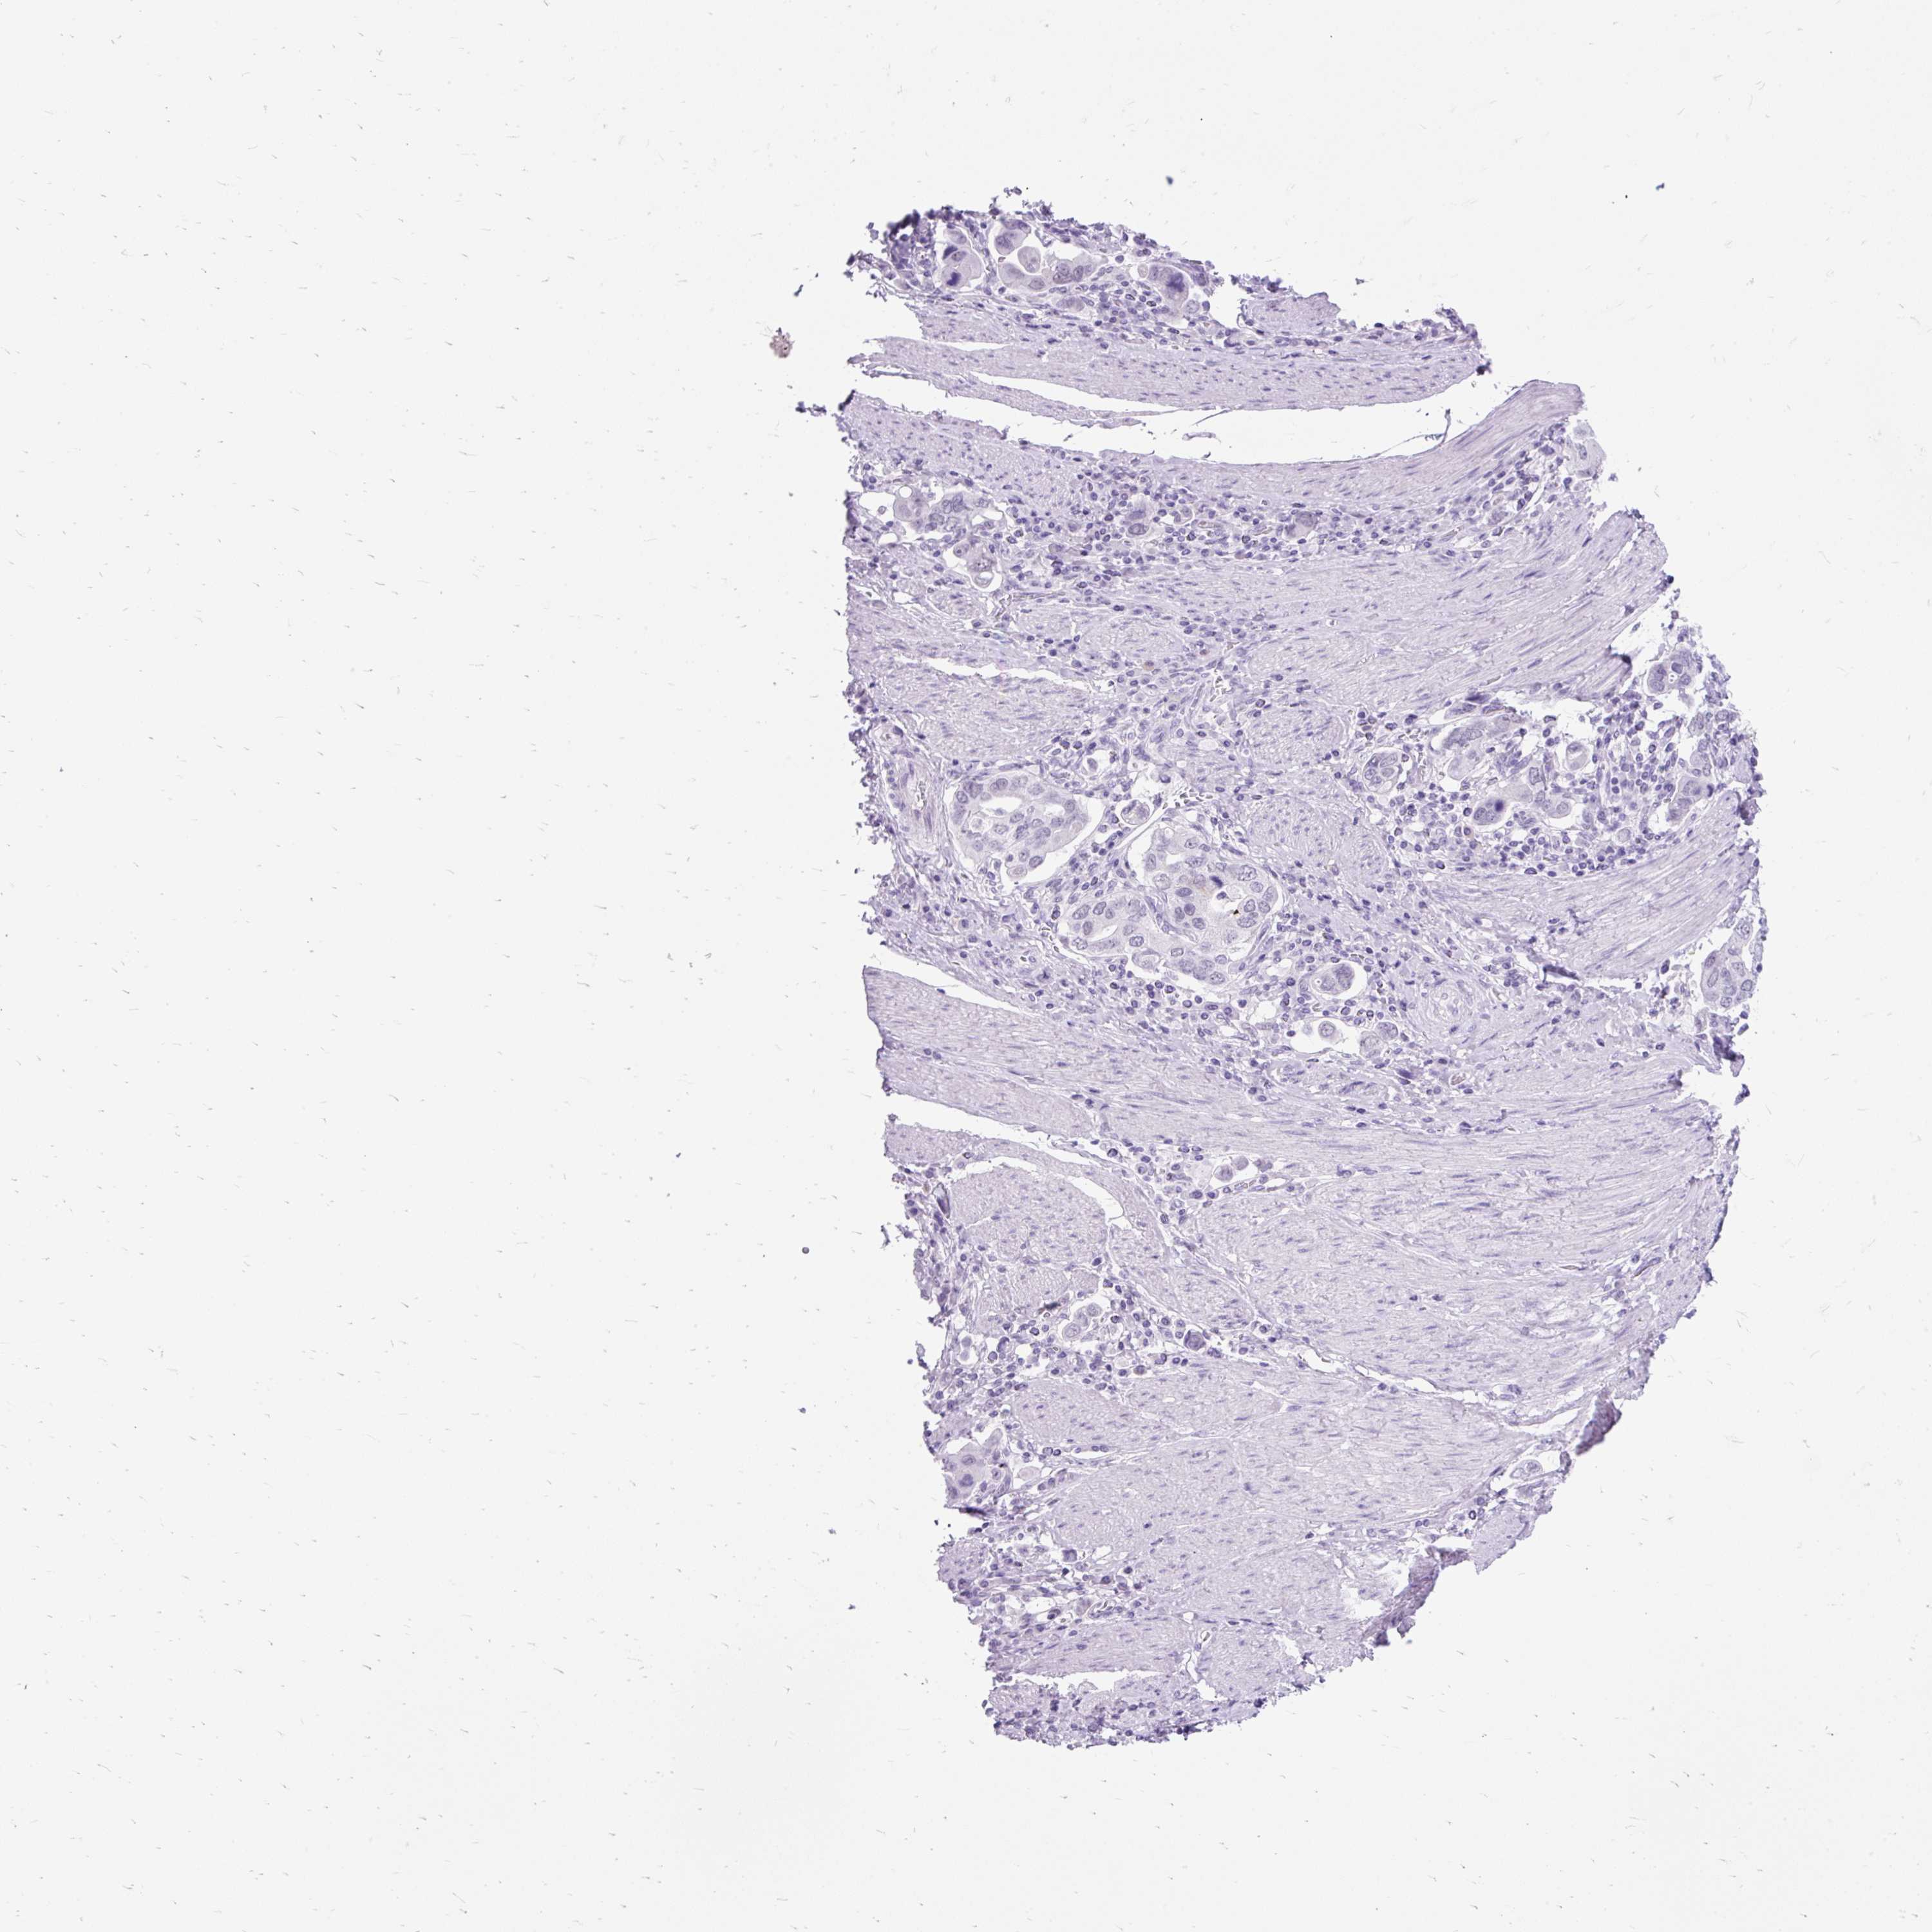

STOMACH CANCER - Protein expressioni

A mouse-over function shows sample information and annotation data. Click on an image to view it in a full screen mode. Samples can be filtered based on level of antibody staining by selecting one or several of the following categories: high, medium, low and not detected. The assay and annotation is described here.

Antibody stainingi

Antibody staining in the annotated cell types in the current human tissue is reported as not detected, low, medium, or high, based on conventional immunohistochemistry profiling in selected tissues. This score is based on the combination of the staining intensity and fraction of stained cells.

Each image is clickable and will lead to virtual microscopy that enables deeper exploration of all samples and also displays staining intensity scores, fraction scores and subcellular localization as well as patient and tissue information for each sample.

Antibody HPA031828

Antibody CAB025686

Staining

High

Medium

Low

Not detected

Intensity

Strong

Moderate

Weak

Negative

Quantity

>75%

75%-25%

<25%

None

Location

Nuclear

Cytoplasmic/membranous

Cytoplasmic/membranous,nuclear

Adenocarcinoma, NOS

Adenocarcinoma, High grade